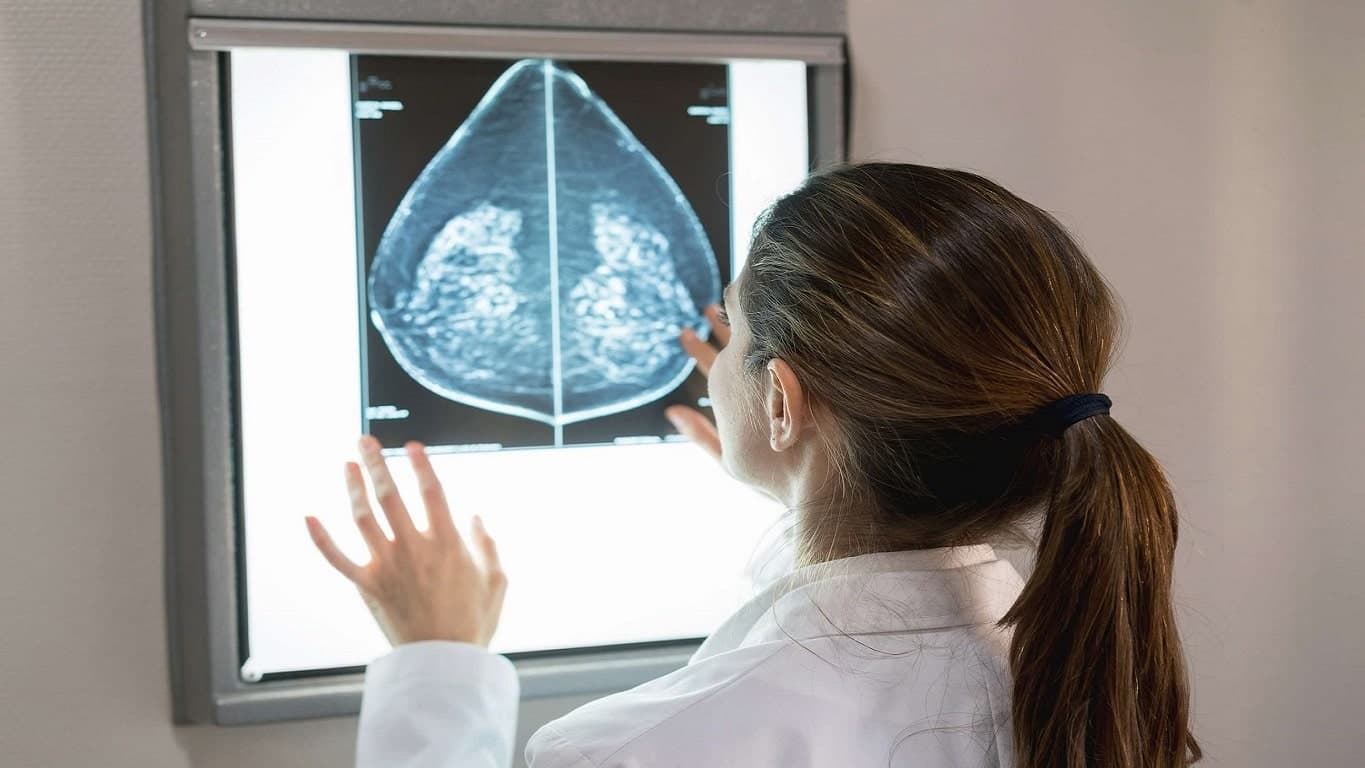

Currently, doctors and radiologists face significant challenges in the diagnostic process due to the time-consuming tasks of comparing medical images, detecting tumors, and monitoring disease progression without available software assistance. This situation is exacerbated by the increasing volume of medical imaging data, demanding faster and more accurate diagnoses. VIDA Medicals addresses this issue by offering software and AI solutions that aid in cancer detection, tumor segmentation, calcification identification, and provide options for monitoring disease progression and comparing medical images. This technology aims to alleviate the pressure on healthcare professionals, improve patient outcomes, and enhance overall healthcare efficiency.